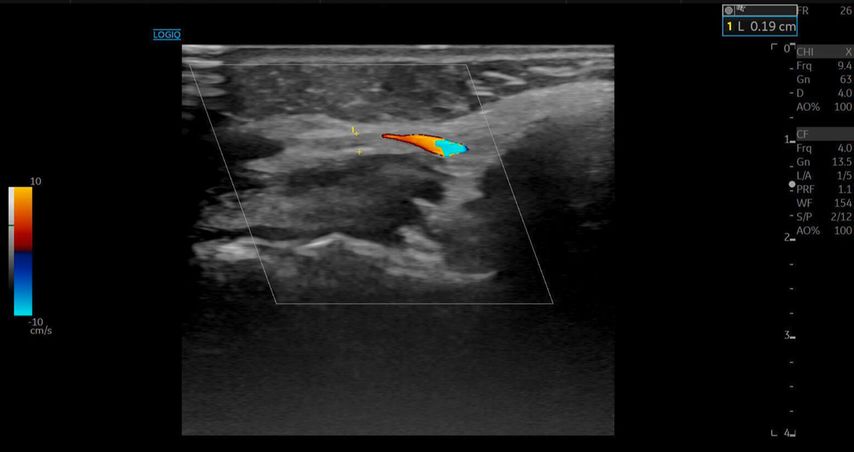

Bei der Erstvorstellung in unserer Praxis zeigten sich eine ausgeprägte Livedo racemosa der Nase sowie ischämische Verfärbungen der linken Wange mit sichtbarer Epidermiolyse. Eine Duplexsonografie ergab eine Hypervaskularisation der Nasenwurzel, ein Hyaluron-Depot sowie Zeichen einer verminderten Mikrovaskularisation («quiet zone») im Bereich der A. angularis.

Die A. facialis imponierte beim Austritt im Bereich des Musculus masseter (oberhalb der Kieferlinie) vasospastisch mit einem maximalen Durchmesser von 1mm. Die abgeleitete systolische Spitzengeschwindigkeit betrug trotz der bestehenden Ischämie 20cm/s, ohne enddiastolische Komponente, was auf eine weitere periphere Vasokonstriktion hindeutete (Abb. 2 und 3).